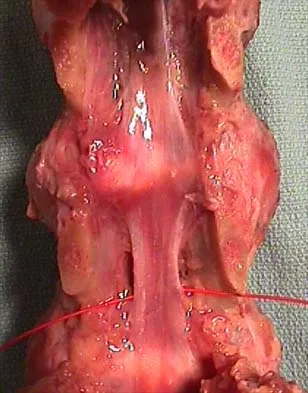

Question 21

A 33-year-old woman sustains a C6 burst fracture diving into a swimming pool, resulting in a complete spinal cord injury. The canal compromise is shown in Figures 8a and 8b. Functional recovery would be maximized with

Explanation